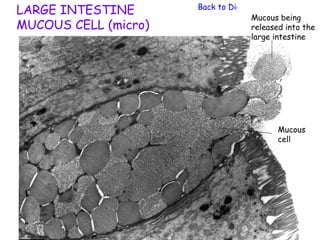

LARGE INTESTINE       Back to Digestive System

Mucous being

MUCOUS CELL (micro)                 released into the

large intestine

Mucous

cell